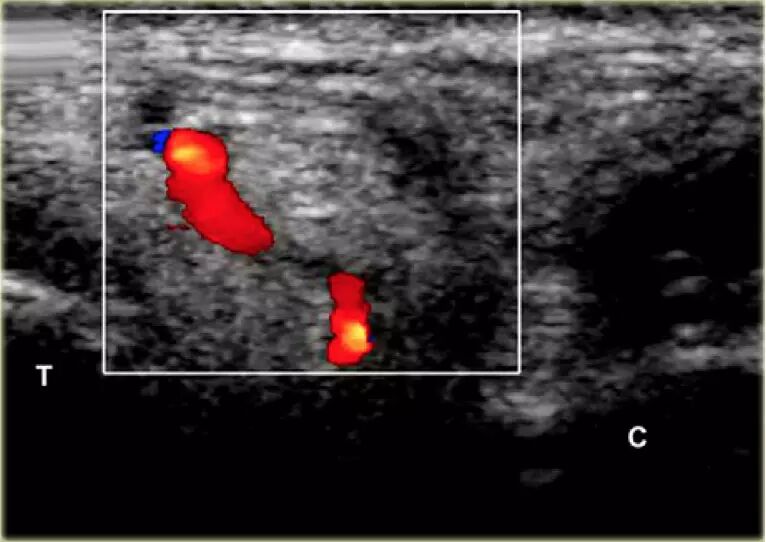

根据炎症的程度,可能存在空间的充血,并且可能存在中间血管可见,这是人们希望避免的。但是这又是比较容易的,特别是彩色多普勒。